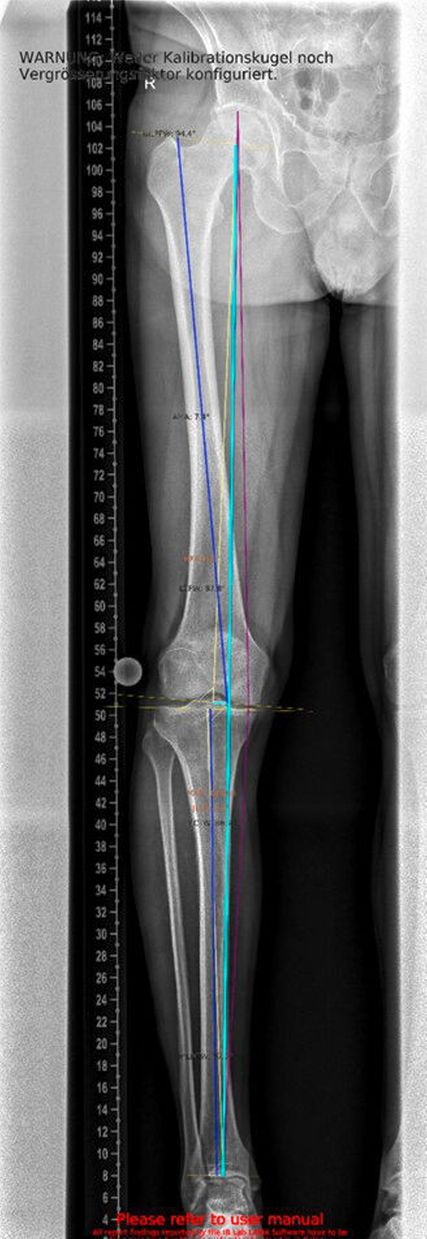

Ein 62-jähriger Patient stellte sich im März 2025 mit belastungsabhängigen Knieschmerzen rechts vor. Im MRT zeigte sich eine Läsion des medialen Meniskus, sodass in Zusammenschau mit dem positiven Meniskuszeichen in der klinischen Untersuchung eine partielle Meniskektomie durchgeführt wurde. Die postoperative Phase verlief zunächst unauffällig. Der Patient berichtete über ein beschwerdefreies Intervall von rund sieben Wochen. Anschließend entwickelten sich jedoch erneut zunehmende Schmerzen im rechten Kniegelenk, die eine erneute Vorstellung in der Spezialambulanz erforderlich machten. Er berichtete vor allem über belastungsabhängige Schmerzen im Bereich des medialen Kniegelenks. Daraufhin wurde ein Ganzbeinröntgen zur Beurteilung der Beinachse durchgeführt, hier zeigte sich eine varische Beinachse mit 5 Grad Varus (Abb.1). In der ergänzend durchgeführten MRT-Untersuchung konnte medialseitig eine ausgeprägte Nekrosezone am medialen Femurkondyl nachgewiesen werden (Abb.2). Schlussendlich wurde aufgrund dieses Befundes die Indikation zur Implantation einer medialen Hemischlittenprothese rechts gestellt, die schließlich im August 2025 komplikationslos durchgeführt wurde (Abb.3+4).